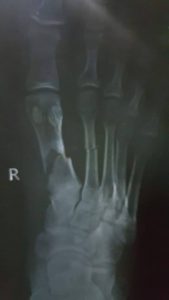

අනතුරට පත් වූ පුද්ගලයාගේ X කිරණ පිටපත් සහ කඩා වැටුණු අනාරක්ෂිත තාප්පයේ ඡායාරූපයක්ද පහතින් දැක්වේ.

අඟුරුවාතොට පොලිස් වසමේ රෙමුණ අඹගහලන්ද පාරේ නිවසක තනා තිබුණු අනාරක්ෂිත තාප්පයක් අසල්වැසි නිවැසියෙකු මත කඩා වැටීමෙන් එම පුද්ගලයාගේ දෙකකුල උකුල් ප්රදේශය බරපතළ ලෙස හානියට පත් විය.

අනාරක්ෂිත තාප්පය කඩා වැටීමෙන් අගතියට පත් පුද්ගලයා දින දහ හතරක් පුරාවට රෝහල් ගතව සිට ශල්ය කර්ම වලට භාජනය වීමෙන් අනතුරුව මේ වන විටත් තමාගේ රැකියාව පවා සිදුකර ගැනීමට නොහැකිව ඔත්පල ව සිටින අතර අනාරක්ෂිත තාප්පය පවත්වාගෙන ගිය පුද්ගලයා කෙරෙහි පානදුර ඉහළ පොලිස් නිලධාරියා දැක්වූ කරුණාව අගතියට පත් පාර්ශවය කෙරෙහි නොදැක්වීම බරපතල ගැටලුවකි.